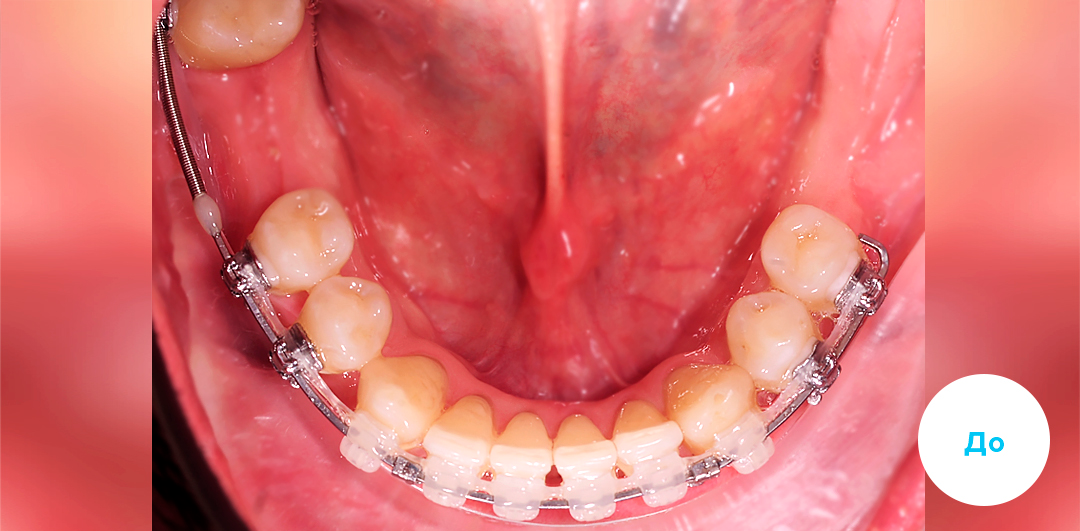

Результаты лечения